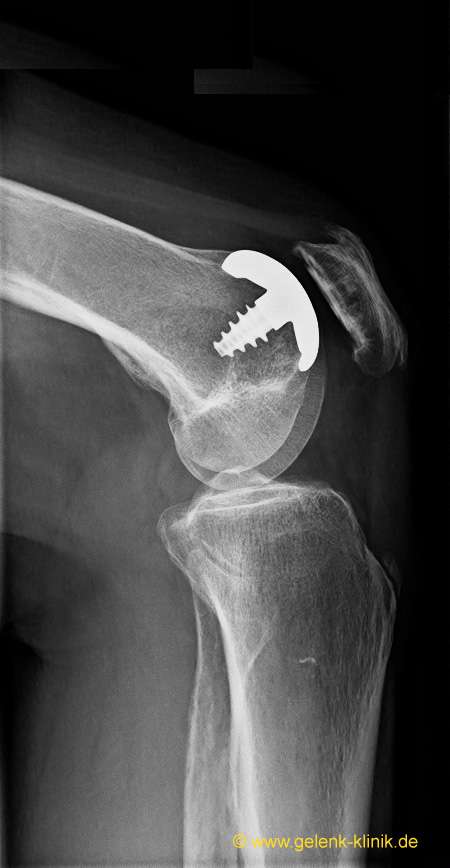

Seitliches Röntgenbild: Links ist die Kniescheibe zu sehen. Die Oberflächenersatzprothese (Hemicap) kann kleine lokale Knochen-Knorpelschäden überdecken und das Fortschreiten der Kniearthrose eindämmen. © Prof. Dr. med. Ostermeier

Das aufgeraute Gewinde des Hemicap-Schaftes erlaubt ein stabiles und zementfreies Einheilen des umgebenden Knochens. Diese Oberflächenersatzprothese kann kleinere Knochen- und Knorpelschäden direkt überdecken. Die minimalinvasive OP-Technik sorgt für eine im Vergleich zur Vollprothese schnelle, schmerzarme und komplikationsfreie Heilung. Der deutlich sichtbare Gelenkspalt im Röntgenbild zeigt, dass die gelenkschützende Knorpelschicht in diesem Kniegelenk noch völlig intakt ist. © Prof. Dr. med. Ostermeier